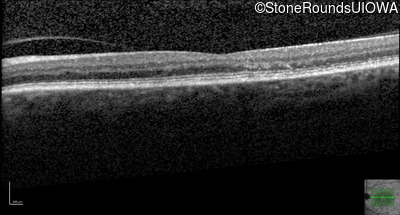

Age at visit: 59 years (Visit 3)

OD OS